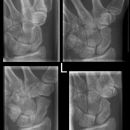

Handgelenk seitlich

Beurteilungskriterien

• Neigung der distalen Radiusgelenkfläche in der Sagittalebene: 10 – 15°

• Kontinuierliche Verlängerungsachse durch Radius, Lunatum, Capitatum und Os metacarpale III. Kontinuität von Handrücken und Unterarmrückfläche (Luxation, nicht-exakte Einstellung? -> Proc.styloideus ulnae im hinteren Radiusdrittel?)

• Scapholunärer Winkel 30 – 60°

• Verstreichen und Ventralverlagerung der volaren Fettstreifen vor dem M.flexor digitorum profundus und M.pronator quadratus

• Grundsätzlich gilt: unklare Verhältnisse -> CT-Indikation

Beispiele

Smith-Fraktur (2) volare Fragmentabkippung

Colles- Fraktur (2) dorsale Fragmentabkippung

Chauffeur-Fraktur (2) radialer Keilbruch

Barton-Fraktur (2) intraartikulär, dorsales Kantenfragment

Reversed Barton-Fraktur (2) intraartikulär, volares Kantenfragment